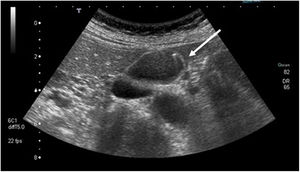

| Cholesterol polyp | Cholesterol deposits in the interior of the macrophages in the lamina propia of the gallbladder wall | Hyperechoic structure, no posterior acoustic shadow, and does not vary position with patient movement (Fig. 1) |